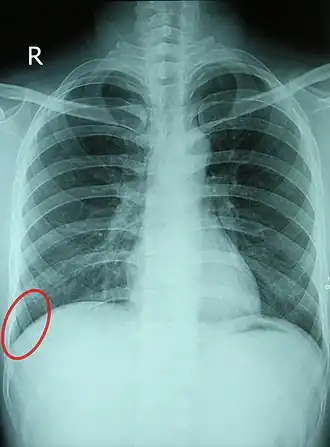

Chest X-ray of a 30-year-old healthy man, with the costodiaphragmatic recess label in red ellipse

Comparison between a normal costophrenic angle on the patient's right, and an obscured costophrenic angle (circled) on the patient's left, due to pneumonia with parapneumonic effusion.

In anatomy, the costophrenic angles are the places where the diaphragm (-phrenic) meets the ribs (costo-).

Each costophrenic angle can normally be seen as on chest x-ray as a sharply-pointed, downward indentation (dark) between each hemi-diaphragm (white) and the adjacent chest wall (white). A small portion of each lung normally reaches into the costophrenic angle. The normal angle usually measures thirty degrees.